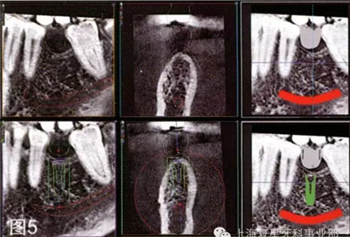

通過對牙冠的最后評估,考慮到重要的解剖結(jié)構(gòu),如下齒槽神經(jīng)和血管,設(shè)計種植體數(shù)字化的通過對牙冠的最后評估,考慮到重要的解剖結(jié)構(gòu),如下齒槽神經(jīng)和血管,設(shè)計種植體數(shù)字化的三維位置,獲得最便捷的修復(fù)和外科手術(shù)結(jié)果。然后將該虛擬設(shè)計的牙冠用于放射線模板(圖5)。

圖5:種植體的數(shù)字化三維位置的多面觀。注意如何用設(shè)計的虛擬冠作為數(shù)字化射線模板

可使用口腔內(nèi)表面掃描來設(shè)計治療方案,同時可用錐形束來三維重建進行檢查,以確保植入位置最佳,避免發(fā)生任何骨開窗或骨開裂的可能(圖6a-6b)。